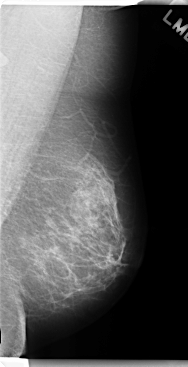

C_0251_1.LEFT_MLO

LEFT_MLO LINES 4760 PIXELS_PER_LINE 2440 BITS_PER_PIXEL 12 RESOLUTION 50 NON_OVERLAY